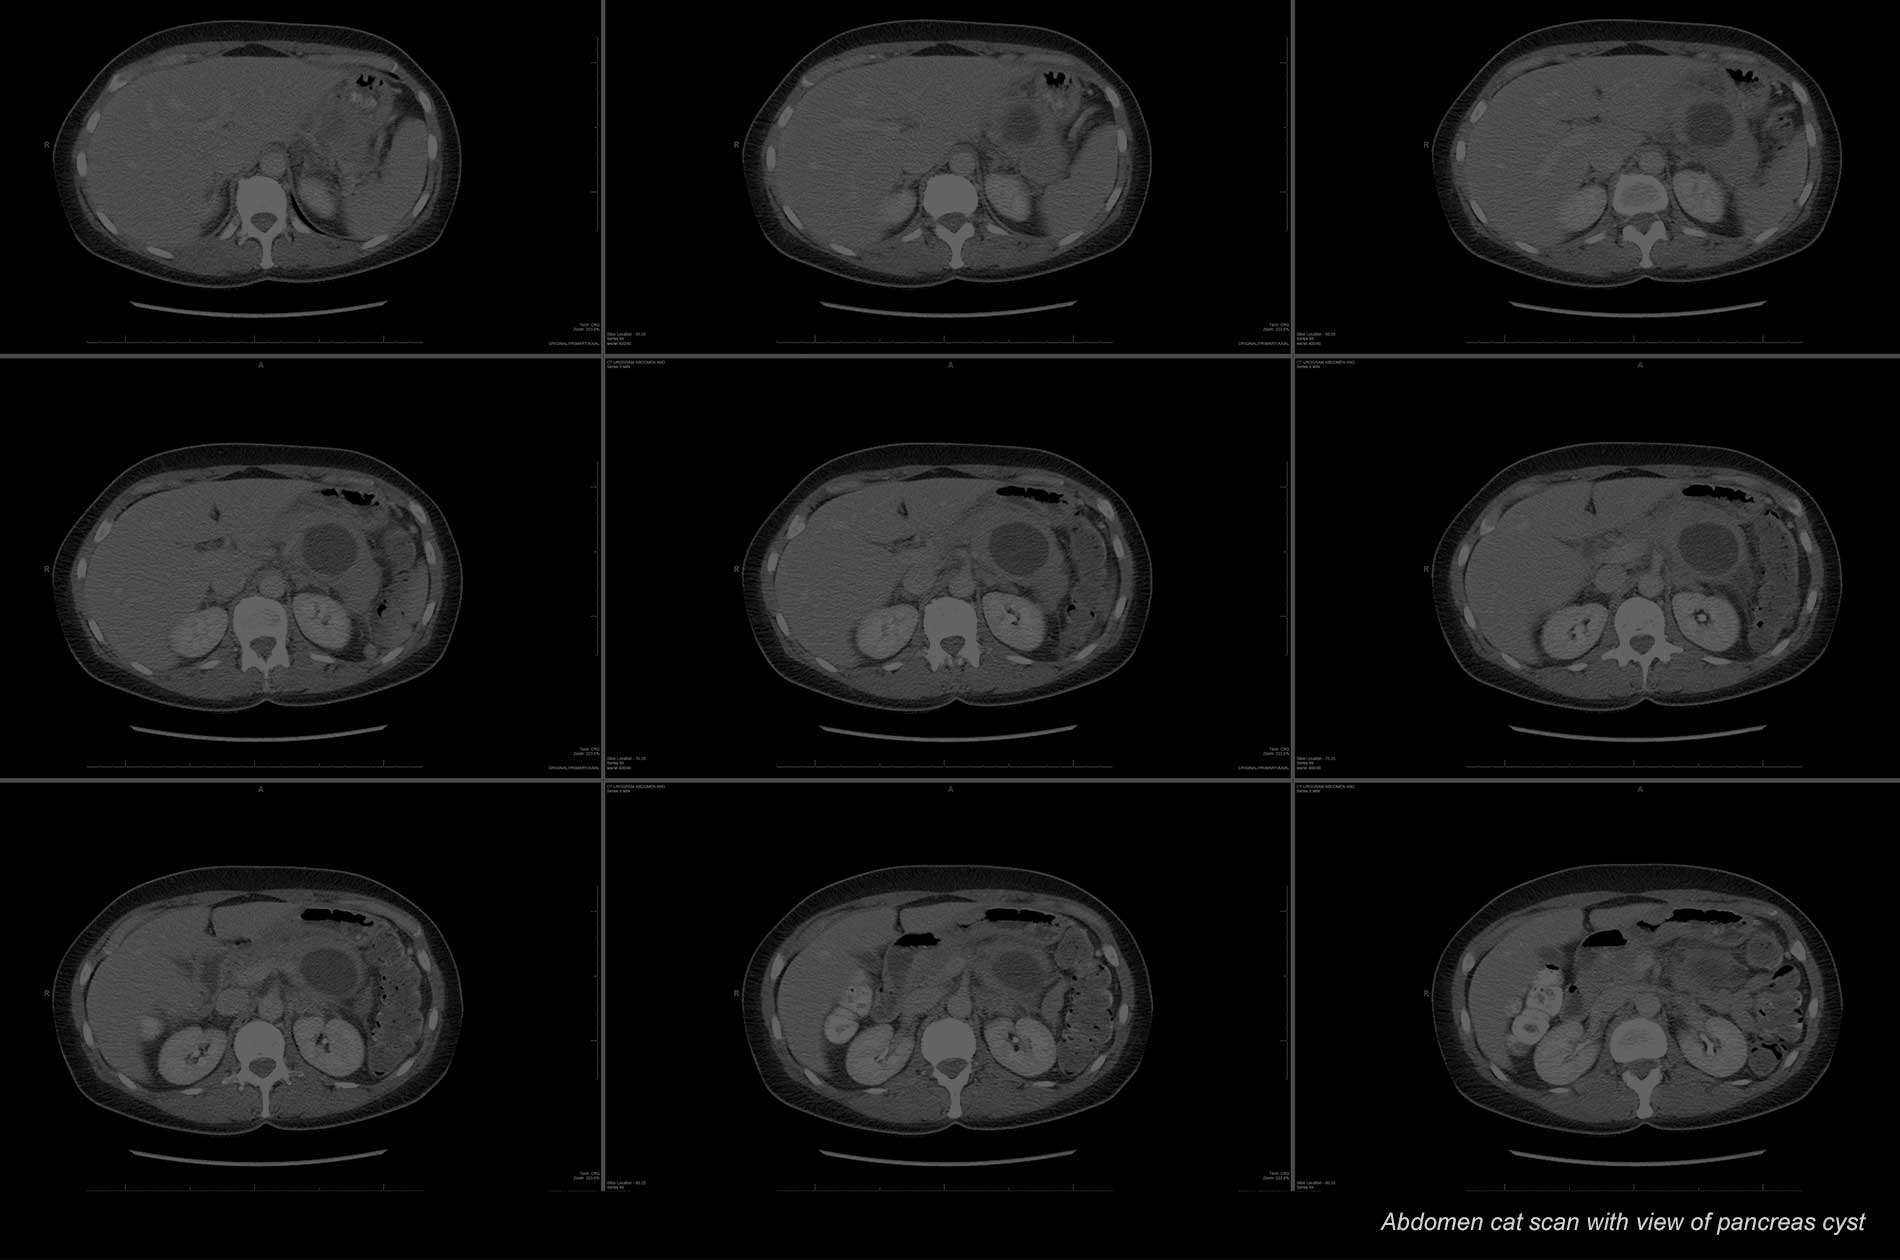

Pancreatic cancer abdominal ct scan. Computed tomography ct scan the ct scan makes detailed cross sectional images of your body. A scanner takes multiple x ray pictures and a computer reconstructs them into detailed images of the inside of the abdomen. In addition to surgical management of pancreatic and related cancers dr.

Ct scans are often used to diagnose pancreatic cancer because they can show the pancreas fairly clearly. To help you prepare heres a look at what to expect. A ct scan of the tummy abdomen can show whether there any changes in the pancreas or nearby structures such as the liver.

It can show changes or abnormal areas in your pancreas and liver. Anatomy of the pancreas. You might have this test to find out if you have pancreatic cancer or to see how big it is and whether it has spread.

Winter t reats other upper gastrointestinal malignancies and abdominal tumors. Ct scans of the pancreas are useful in the diagnosis cancer of the pancreasand pancreatitis.